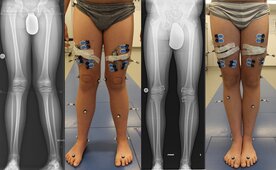

Die Fehlstellungen lassen sich anhand einer klinischen Untersuchung feststellen: Röntgenaufnahmen, eventuell weitere bildgebende Verfahren (MRT, CT) und eine instrumentelle dreidimensionale Ganganalyse können zur genaueren Beurteilung erforderlich sein und die genaue mechanische Achse des Beines darstellen. Nach Auswertung der Befunde werden diese besprochen und ein individueller Therapieplan entworfen.

Röhrenknochen verfügen jeweils an ihren gelenknahen (= körpernahen und körperfernen) Enden über sogenannte Wachstumszonen. Ziel der wachstumslenkenden Behandlung ist es, das Wachstum der betroffenen Knochen in dieser Zone mittels kleiner Implantate derart zu lenken bzw. zu bremsen, dass innerhalb der folgenden Monate eine Begradigung der Fehlstellung bzw. ein Längenausgleich der Beine erreicht wird.In Studien konnten wir zeigen, dass sich durch die Behandlung auch die Gelenkbelastungen normalisieren: